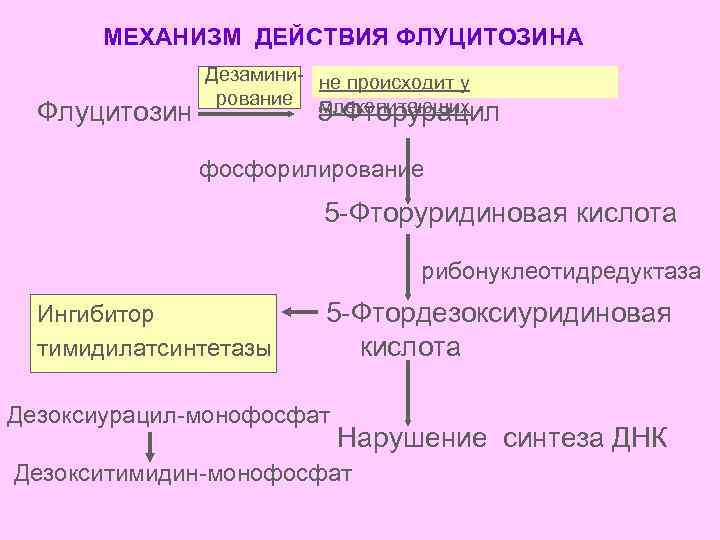

МЕХАНИЗМ ДЕЙСТВИЯ ФЛУЦИТОЗИНА Флуцитозин Дезамини- не происходит у рование млекопитающих 5 -Фторурацил фосфорилирование 5 -Фторуридиновая кислота рибонуклеотидредуктаза Ингибитор тимидилатсинтетазы 5 -Фтордезоксиуридиновая кислота Дезоксиурацил-монофосфат Нарушение синтеза ДНК Дезокситимидин-монофосфат